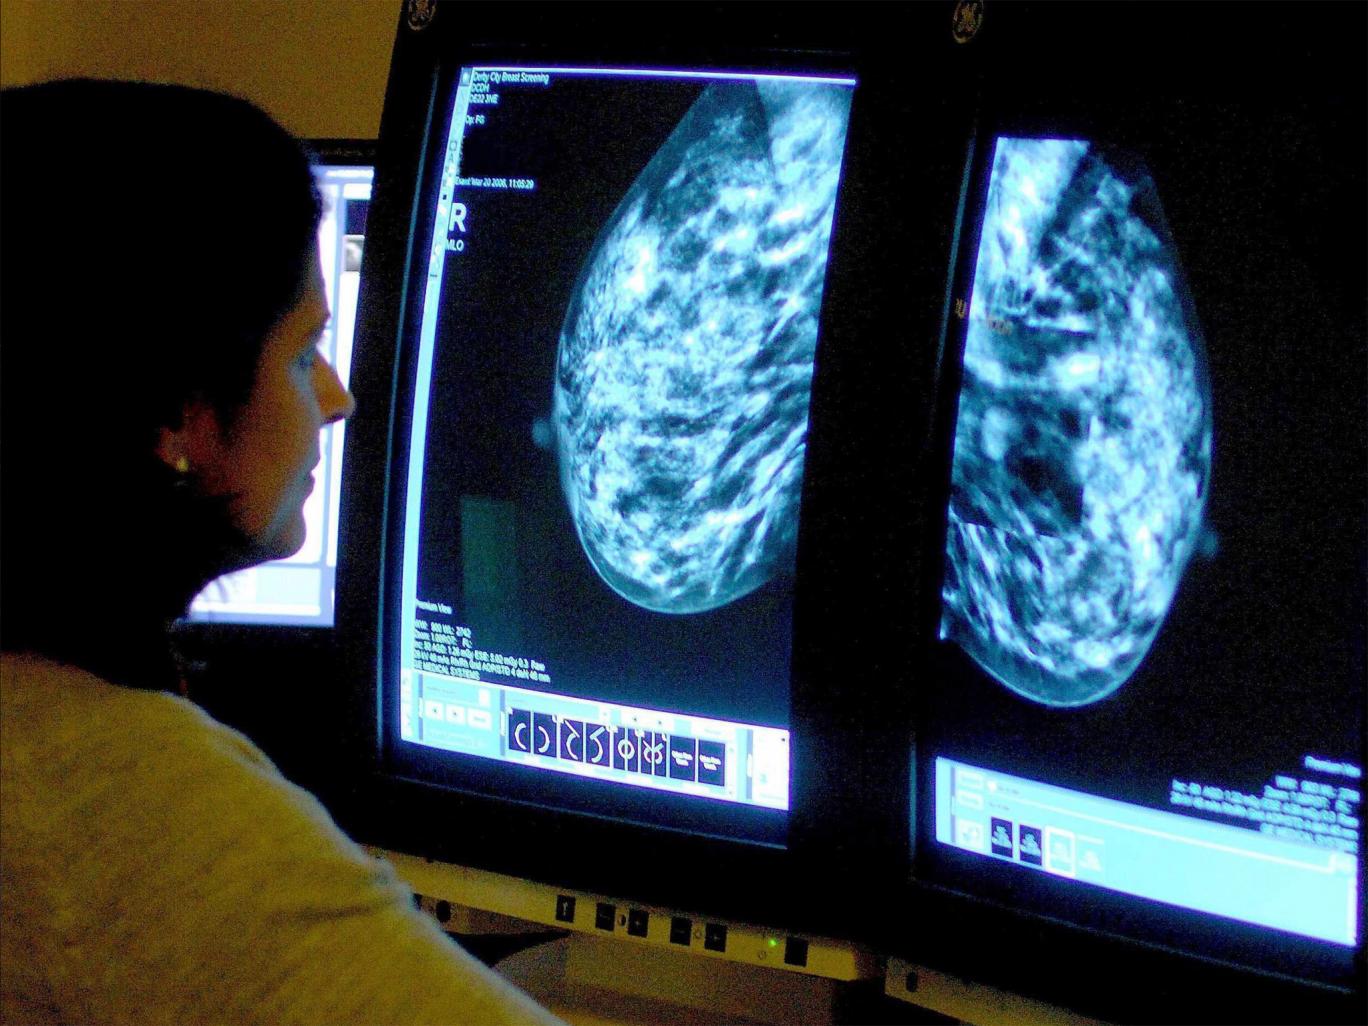

(ĐSPL) - Hai nghiên cứu được dự báo là sự “đột phá” đã được tiến hành bởi Hiệp hội từ thiện về căn bệnh ung thư vú của Anh.

Việc nghiên cứu các thụ thể estrogen (hoóc-môn sinh dục nữ) có thể là “chìa khóa” giải thích tại sao một số dạng ung thư vú không đáp ứng điều trị, theo hai nghiên được trình bày tại Hội nghị chuyên đề nghiên cứu ung thư vú, tại Anh. Các nhà khoa học cho rằng, đây là những phát hiện có tính đột phá về căn bệnh này.

Tổ chức từ thiện Breast Cancer Now đã mô tả kết quả của cả hai nghiên cứu trên là một bước “đột phá” trong hiểu biết về căn bệnh ung thư vú.